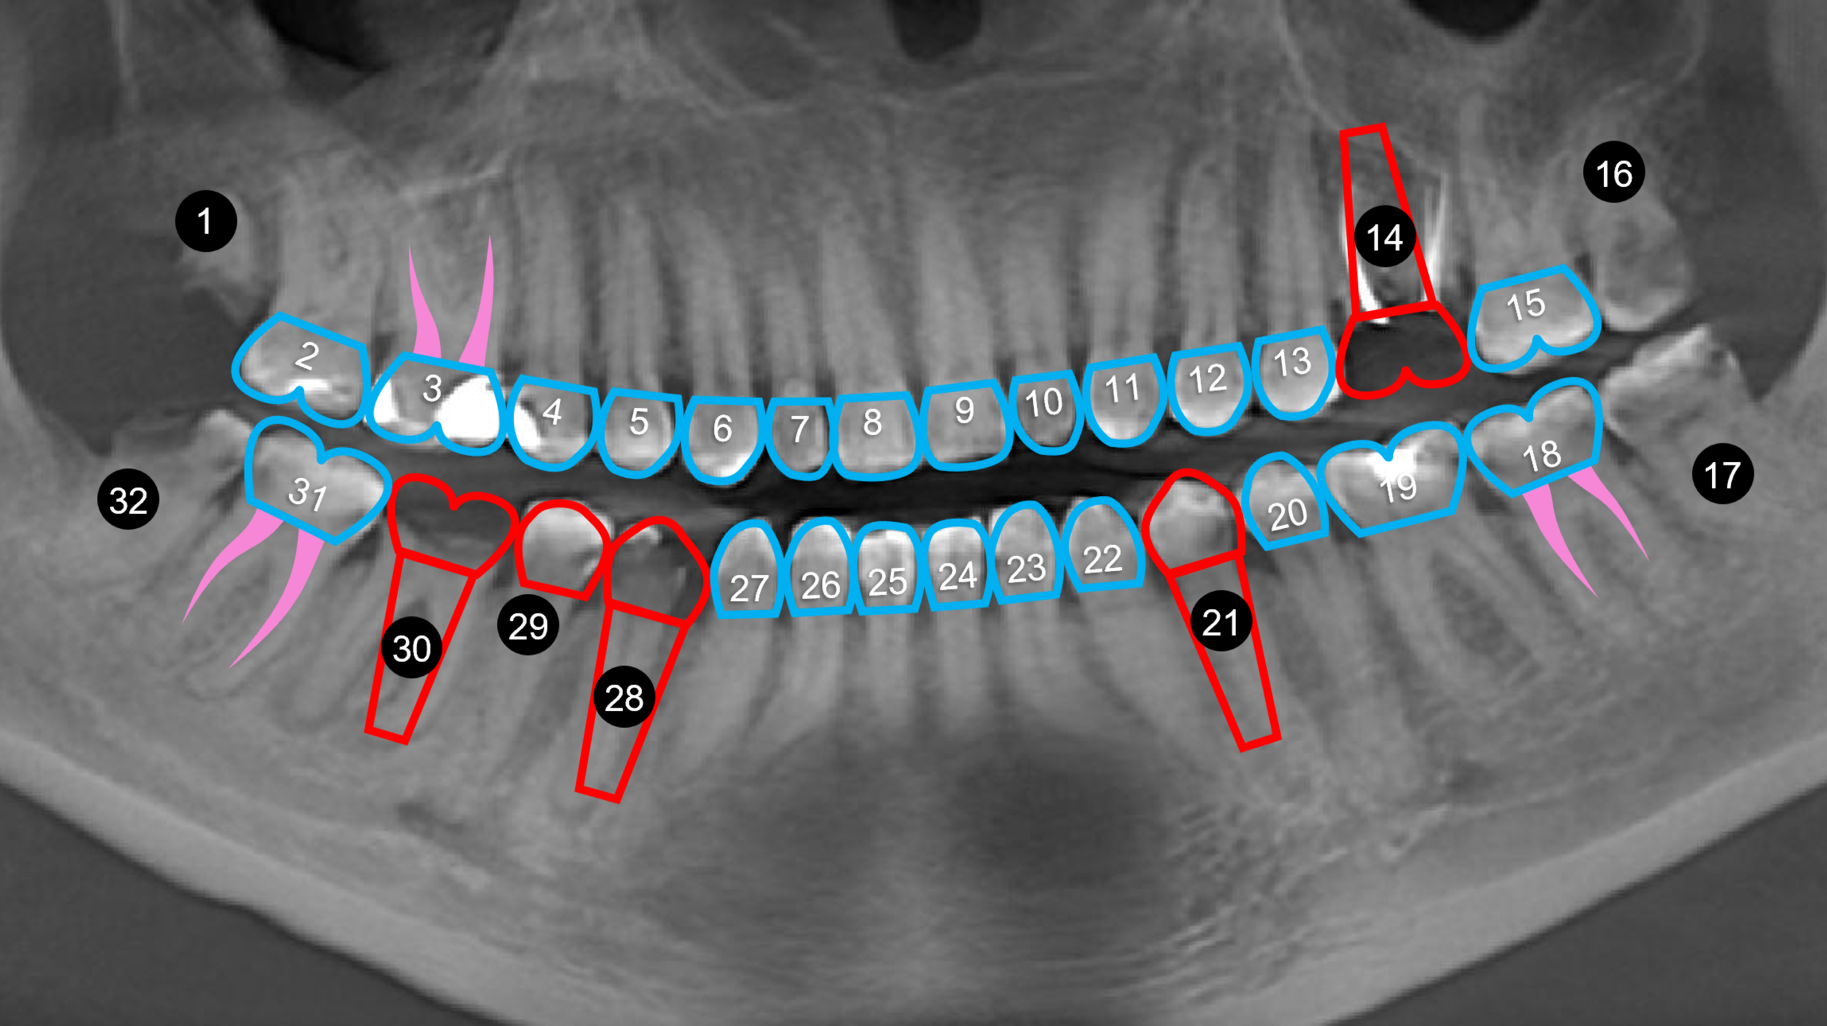

Case review: This 35-year-old female was diagnosed with Sjögren’s syndrome four years ago. She is a cigarette smoker and drinks multiple sodas per day. Her daily oral hygiene is marginal (figures 3–5).

Treatment objectives: Restore or replace all teeth to achieve full function and a natural, healthy-looking smile with a solution that is fixed and will last over the long term (20-plus years).

Today, more than ever, patients expect and hope their dental restoration will solve what has historically been a lifetime cycle of dental problems and expense. In this case, a straightforward, conventional restorative treatment plan that focuses on restoring the patient’s natural teeth may not make the most sense long term. After comparing both restorative paths, the full-arch implant option would likely prove to have a better prognosis, lower cost, and require much less time and fewer appointments.